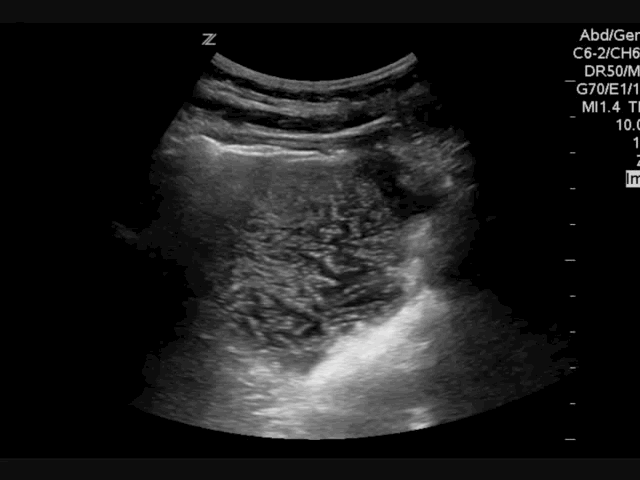

#Sono of the Week: SBO, Stomach Pulse #pocus #foamed #foamus #meded #ultrasound

Small bowel obstruction